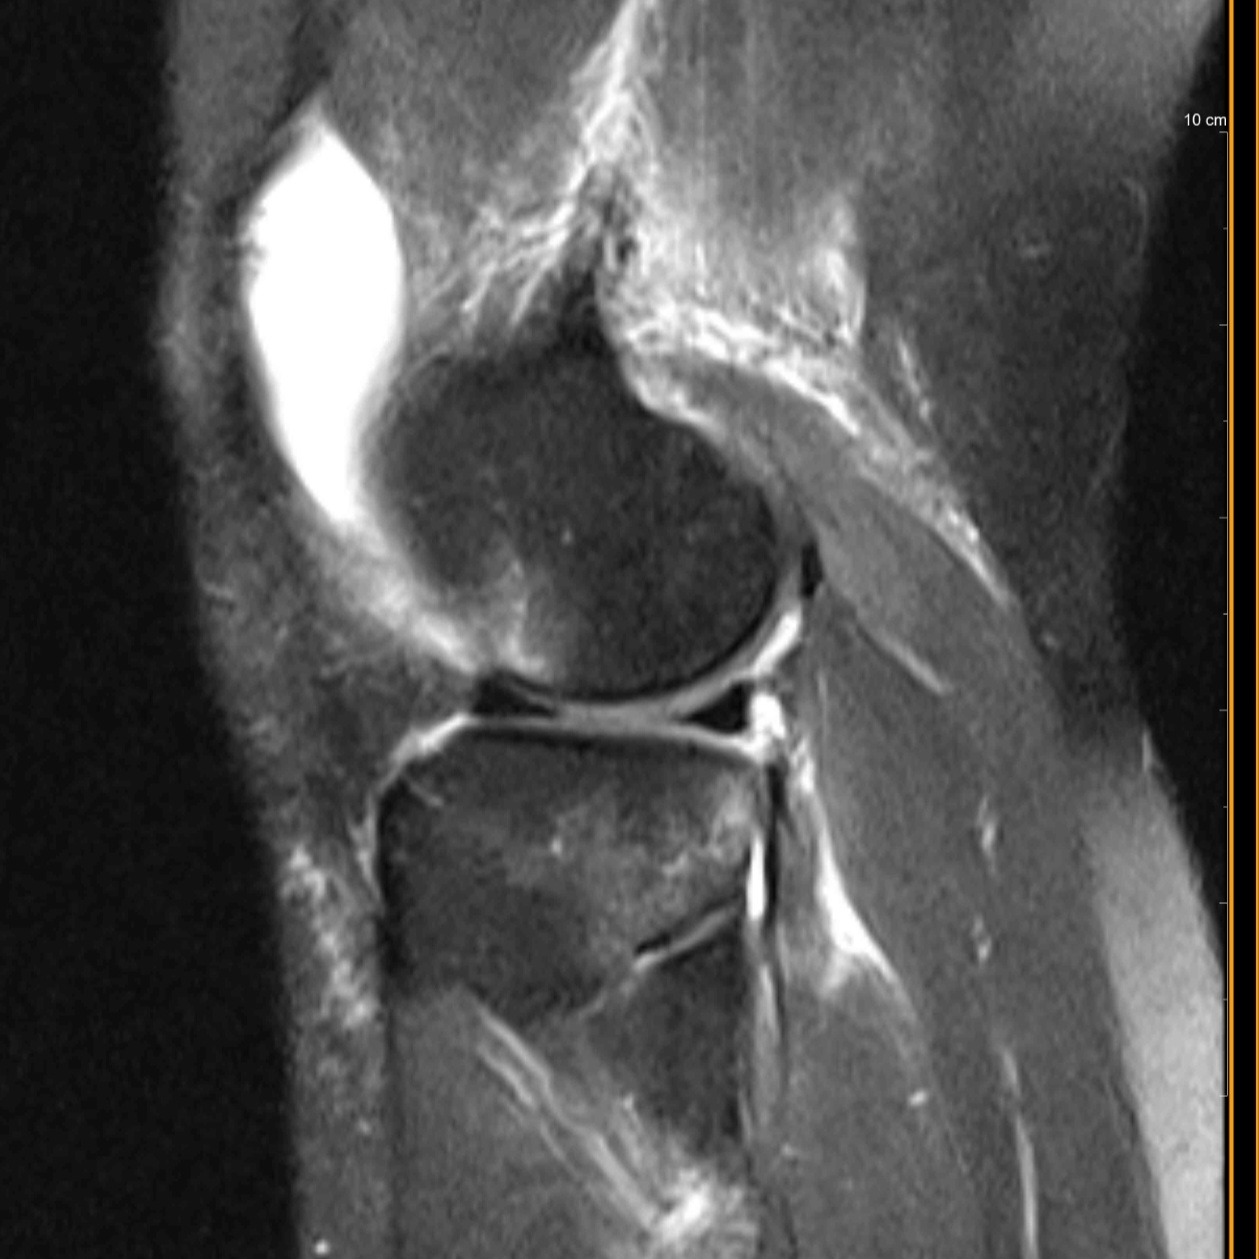

Dawn, my adult daughter, has been through an incredibly difficult time recently. She suffered a complete tear of her ACL while riding her dirt bike two months ago and now needs ACL reconstruction surgery using a cadaver ligament. To make matters worse, just two days ago, she was in a car accident when a young driver ran a red light and totaled her car. The other driver did not have insurance or a license, leaving Dawn without transportation and with even more stress on her shoulders.